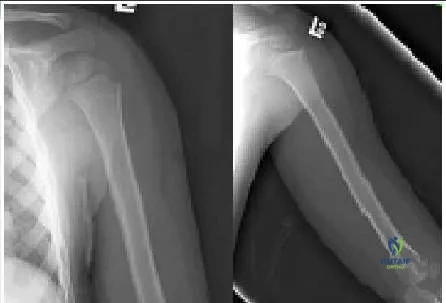

A 5-year-old boy was imaged after being struck by a car. His radiographs (Slide) indicate which of the following diagnoses:

Correct Answer: Normal humerus

Explanation:

The proximal humeral physis has two planes and two ossification centers (in this way, it is analogous to the proximal femur).

When seen in some projections, the more distal extent of the physis may produce a lucent line. The smooth nature and characteristic location of the line should allow surgeons to make the correct interpretation. The two ossification centers of the humeral head may be misinterpreted as a fracture. This patient had a greenstick fracture of the clavicle (not included on this field), which was not noticed, and a humeral fracture was incorrectly diagnosised.